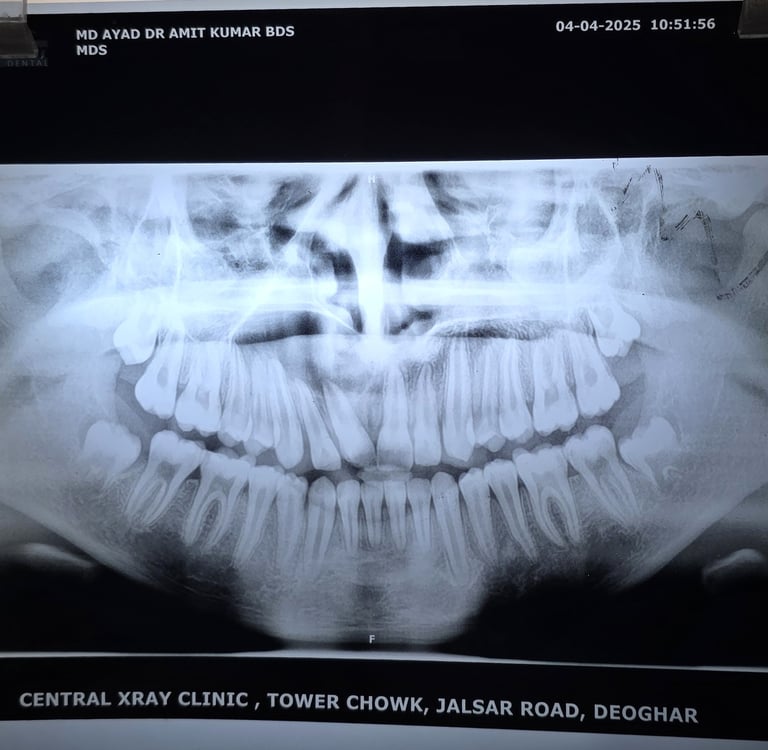

Radiographic Findings (Insert X-ray or CBCT):

Well-defined 4 cm radiolucent lesion extending from central incisor to premolar

Root resorption noted in adjacent teeth

📌 Alt Text: Large radicular cyst involving anterior maxilla in a 15-year-old